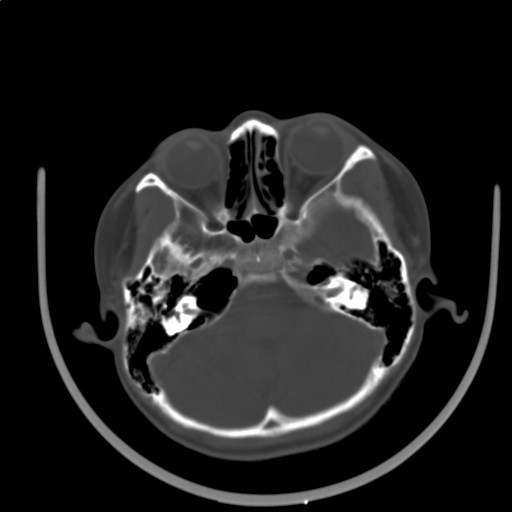

标题: PED3416:F,12Y,智力下降,学习成绩差,8个月时发过高烧。

右侧半球萎缩,软化,多量脑回样钙化,考虑颅面血管瘤病,建议dsa检查

右侧半球萎缩,软化,多量脑回样钙化,同侧颅盖板障增宽,考虑颅面血管瘤病,建议dsa检查与化脓性脑膜炎后遗改变鉴别。